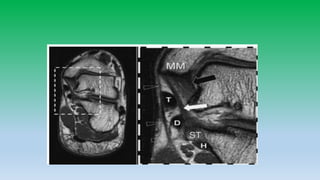

Medial aspect

Tendon: Tibialis posterior

Flexor digitorum longus

Flexor H. longus

Ligaments: Deltoid ligament